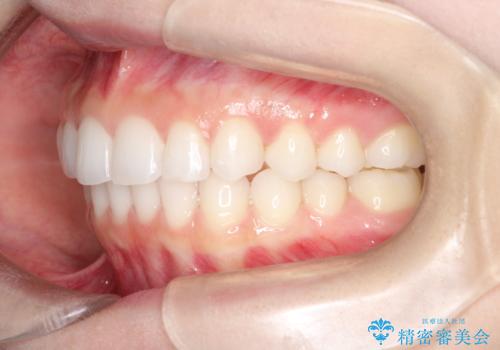

出っ歯の矯正治療 歯を抜かずにインビザラインで

- インビザラインで出っ歯を治したいとの希望がありました。

上顎の歯を全体的に後方に移動させて前歯を引っ込める計画としました。

インビザラインで目立たずに、痛みも少なく矯正治療を終えることができ満足していただけました。